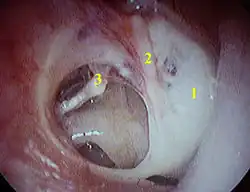

Der Eingriff erfolgt in örtlicher Betäubung oder Allgemeinnarkose. Es wird entweder durch den Gehörgang nach einem kleinen Schnitt im Gehörgangseingang oder nach einem Schnitt hinter dem Ohr operiert. Die Operation erfolgt unter dem Operationsmikroskop. Mitunter muss eine knöcherne Einengung des Gehörganges mit einem Diamantbohrer aufgebohrt oder einem sogenannten Löffel abgetragen werden, damit das Trommelfell vollständig einsehbar wird. Wenn keine Otosklerose vorliegt, der Steigbügel also normal beweglich und intakt ist, liegt oft ein Defekt des langen Ambossfortsatzes vor. Der Amboss wird dann entnommen und sein Körper zwischen Steigbügel und dem langen Hammergriff positioniert. Eine unterbrochene Gehörknöchelchenkette kann auch durch Prothesen aus Metall, Keramik oder Kunststoff rekonstruiert werden. Hat das Trommelfell ein Loch, wird es mit körpereigener Muskel- oder Knorpelhaut (Perichondrium) oder mit einer Knorpelscheibe verschlossen. Am Ende der Operation wird der Schnitt vernäht und der Gehörgang für 3 Wochen tamponiert.